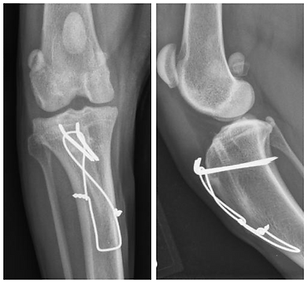

Pins and wires are used to stabilize a tibial tuberosity transposition, the most common surgery for patellar luxation.

Complex stifle trauma repair.